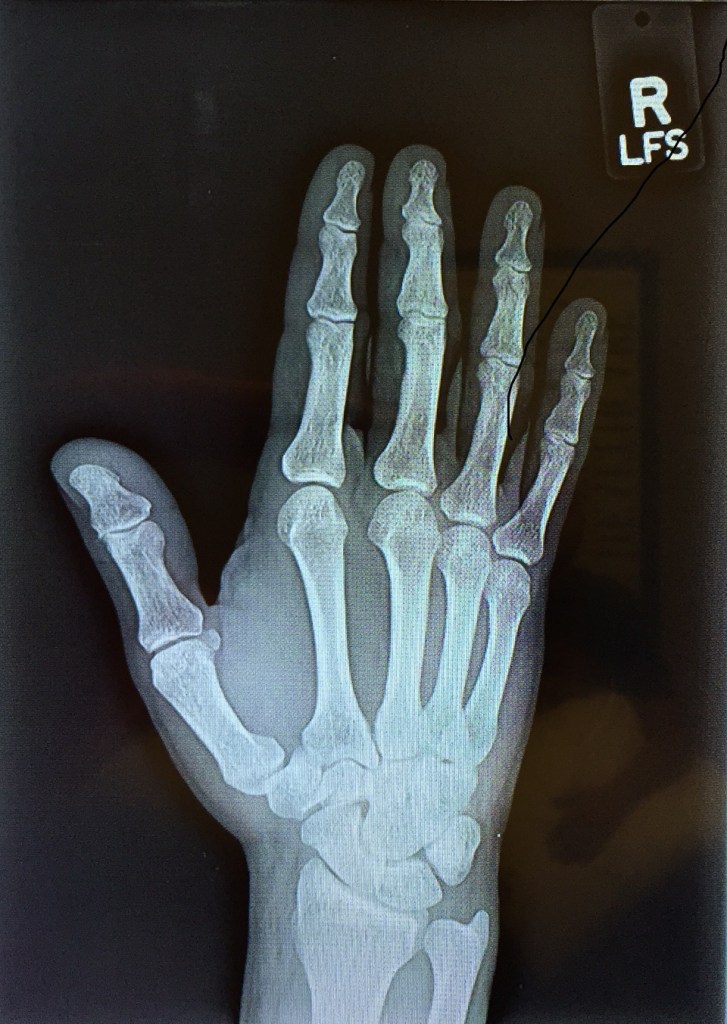

But in the name of scientific studies, pictures of my arm 2 days post incident.

2 days post incident: